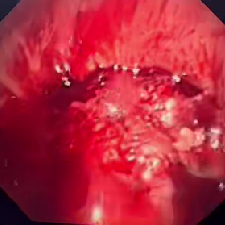

在患者入院后,呼吸与危重症医学科对患者进行了进一步检查。在高流量吸氧80%条件下,患者静息氧饱和度仅能维持在80-85%左右,床旁胸片显示右肺完全不张可能,呼吸与危重症医学科介入团队评估后,决定立即进行急诊手术准备。一方面与家属积极沟通,交代病情和风险,另一方面与麻醉科、微创手术平台联系,做好各环节衔接准备,并沟通抢救预案。2025年5月23日上午,手术在微创中心(第二手术区)正式开始。入室时,患者血氧饱和度仅有68%,伴有神志淡漠,意识恍惚。麻醉师迅速给予全麻,呼吸介入团队马上进行进镜探查。镜下发现患者右主支气管被肿物完全阻塞,伴有血性分泌物。在微创手术室护士的配合下,呼吸介入团队用电圈套器、电刀、冷冻冻切等多种方法,迅速打通了气道。经过45分钟的手术,患者氧饱和度已恢复至97%。手术成功。

右主支气管完全阻塞